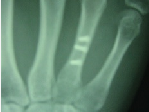

身近になってきた生分解性高分子は、環境にやさしい材料として期待されています。特に、土壌中で自然分解する生分解性トレー等は、環境低負荷材料として一般家庭でも使用されるようになりました。当研究室では、高分子構造と生分解性の基礎メカニズムを解析するとともに、その生分解性を自在に制御する技術を開発しています。この新技術を利用することで、生体組織同様の生体適合性を有するバイオプラスチックを創成し、さらには、人工骨材料、人工筋肉、人工臓器への応用研究を行っています。